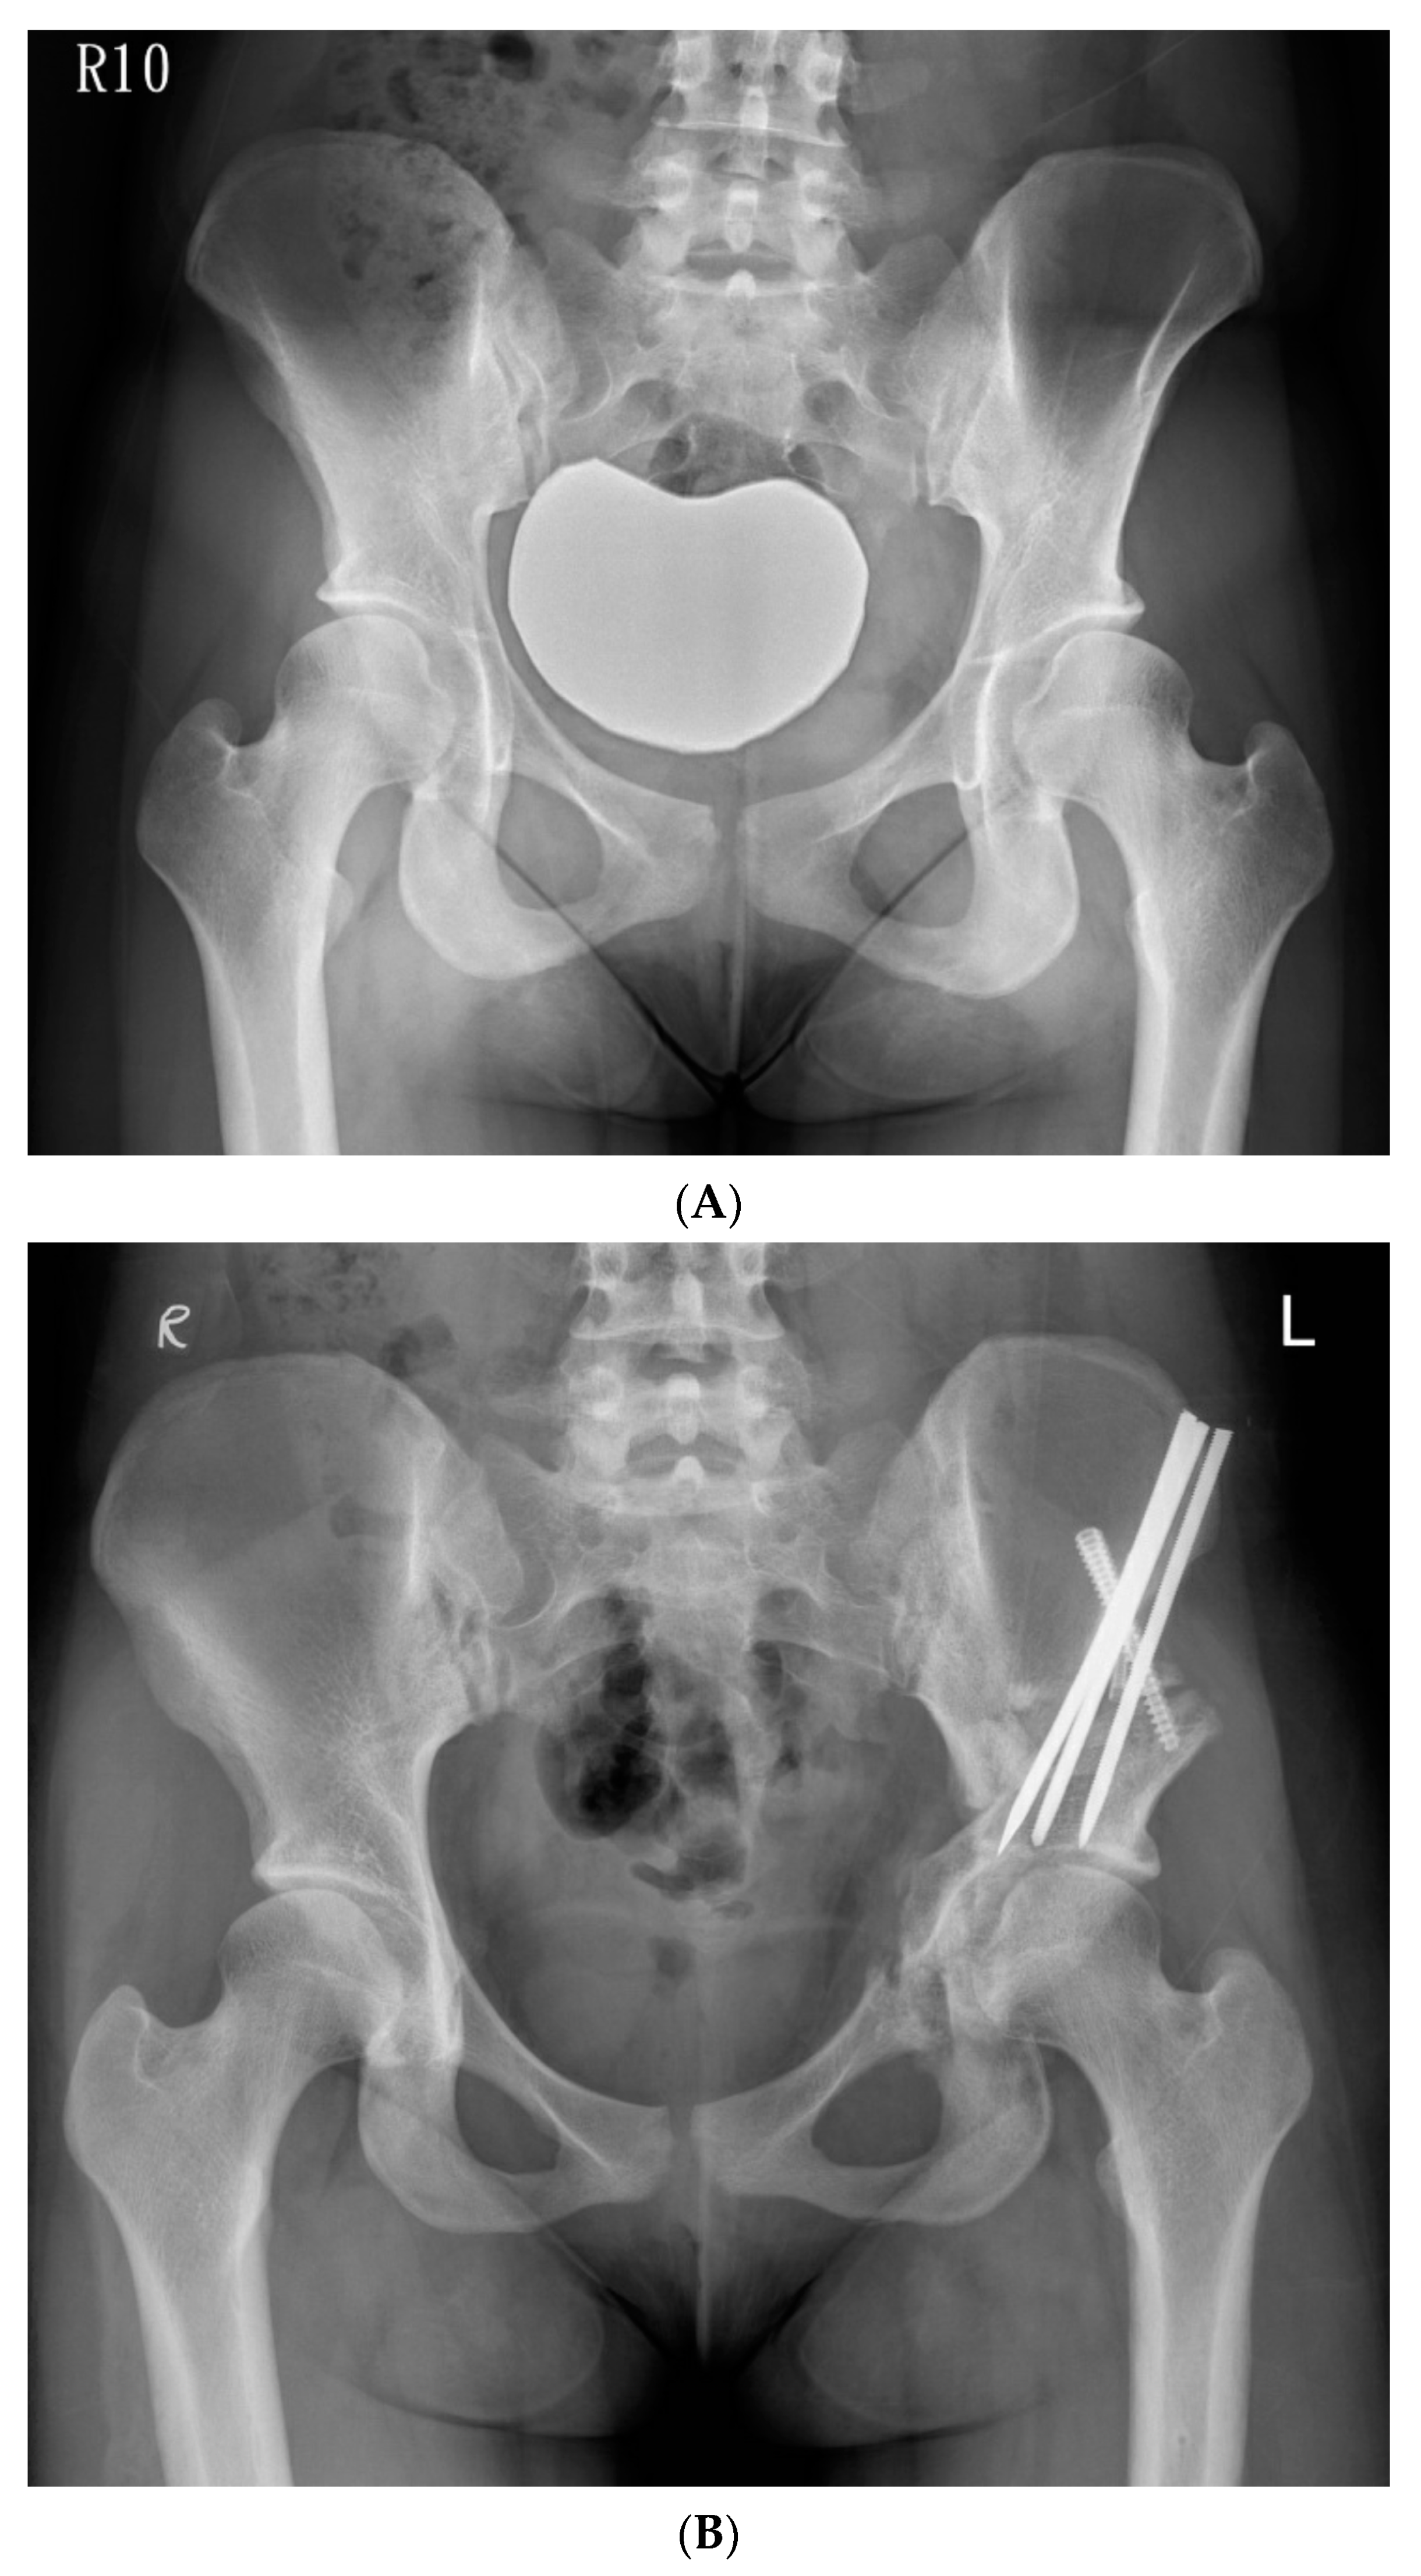

The hip was flexed and adducted to relax the medial soft tissues, and the osteotomy was made through the medial cortex. The osteotomy was extended from the posterior end of the iliac saw-cut and passed over the iliopectineal line, through the medial quadrilateral plate, and parallel to the anterior edge of the sciatic notch as observed through iliac oblique fluoroscopy, and was subsequently directed towards the ischial spine. We used a 30° angled, long-handled chisel to connect the anterior and posterior ischial cuts to complete the osteotomy of the posteroinferomedial corner of the quadrilateral plate. We used a bone clamp as a joystick to manipulate the periacetabular bone by lifting the acetabular fragment slightly towards the ceiling, creating an initial displacement, followed by a three-step movement of lateral, distal, and internal rotation. We inserted the artificial bone graft substitutes into the osteotomy site with multiple 6.0-mm cannulated screws and fixed the ASIS with a 4.5-mm cannulated screw augmented with a transosseous suture. A 1/8” hemovac drain was inserted, and the wound was then closed by layers. (Figure 3A,B).

Figure 3. (A) Preoperative anteroposterior standing radiograph of a 19-year-old woman who underwent Ganz Osteotomy for symptomatic left hip dysplasia. (B) Postoperative anteroposterior standing radiograph showed good coverage of the femoral head.